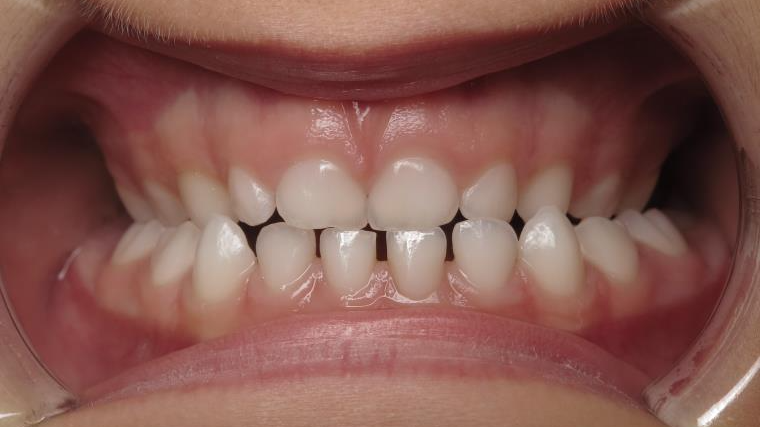

Sélectionnez les différentes étapes du traitement pour comparer et analyser la dentition du cas clinique.

bilan début et en cours de traitement